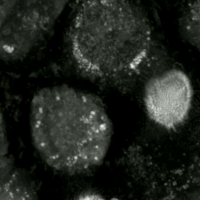

Human prostate cancer cells undergoing ferroptosis

Live-cell imaging has been used to observe the morphological changes that cells undergo during oxytosis/ferroptosis. Initially the cell contracts and then begins to swell. Perinuclear lipid assembly is observed immediately before oxytosis/ferroptosis occurs. After the process is complete, lipid droplets are redistributed throughout the cell (see GIF on right side).[citation needed]